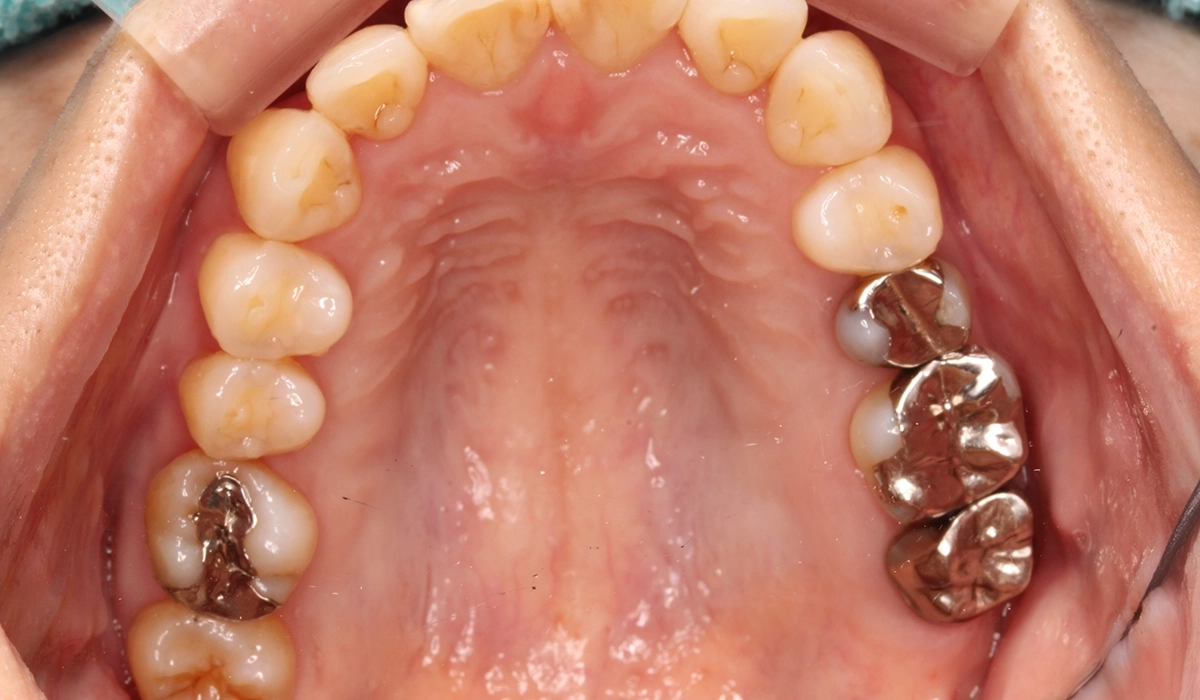

術前:下顎

術後:下顎